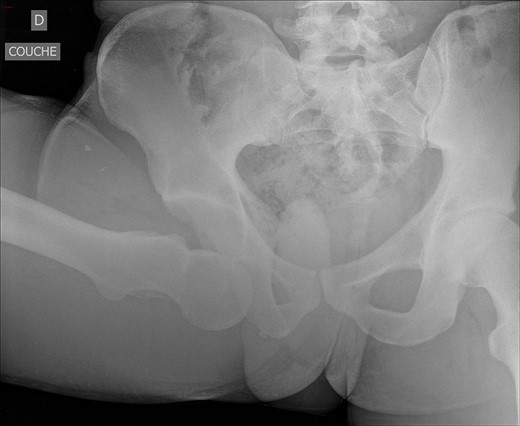

An antero-posterior pelvis radiograph was obtained and showed inferior dislocation of the right femoral head with no associated fracture (Fig. 1). Closed reduction was successfully achieved under general anaesthesia. Reduction consisted of: